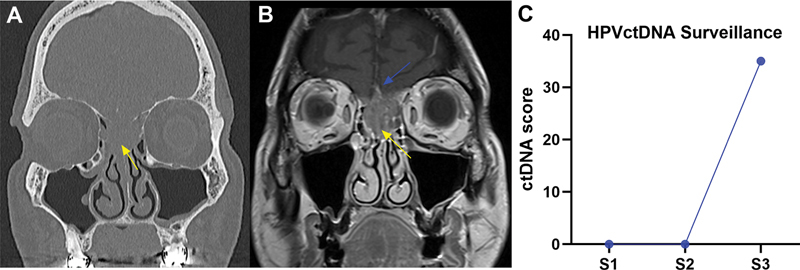

Case reports: We report two cases demonstrating the utility of ctDNA in HPV-mediated sinonasal malignancies. Case 1: 60-year-old male who presented with a large nasal cavity cancer. Pretreatment ctDNA testing yielded a positive tumor tissue modified viral (TTMV)-HPV DNA Score of 67, reflective of the normalized tumor tissue modified viral-HPV DNA fragments/mL of plasma, and pathology confirmed HPV+ SNSCC. Posttreatment surveillance with HPV ctDNA and endoscopy has shown no evidence of disease. Case 2 involves a 64-year-old male with HPV+ neuroendocrine carcinoma who developed recurrence. ctDNA testing, previously negative following initial treatment, scored 35 at recurrence, prompting salvage surgery and adjuvant chemoradiation.